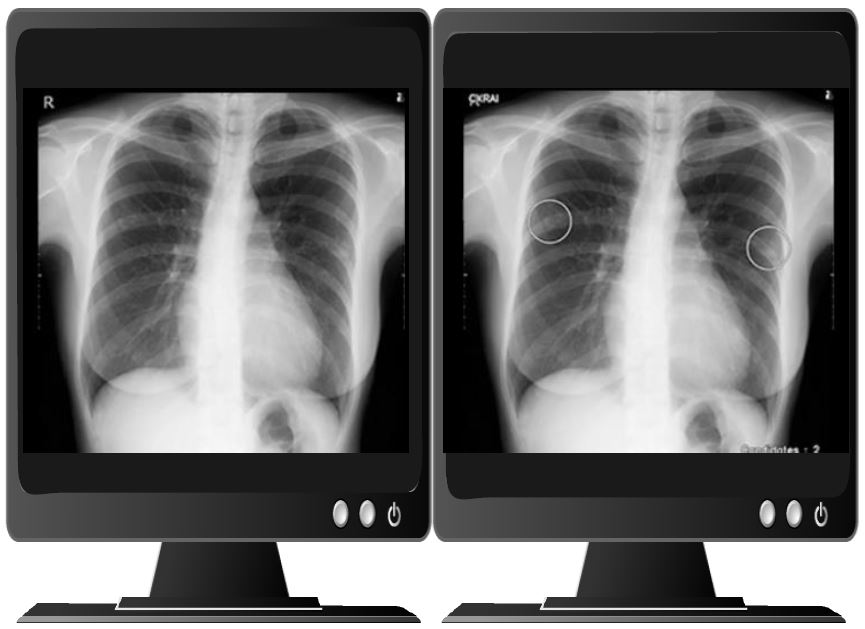

Simple and easy to view, pointing out initial suspicions

Nodules・Masses:Approx 83%

Infiltertive shadows:Approx 80%

By using this product, it is expected to support non-specialist doctors in preventing oversights.

An improvement in sensitivity for physicians is expected. In a comparison with and without this product, an improvement in sensitivity was observed, especially for less experienced doctors.